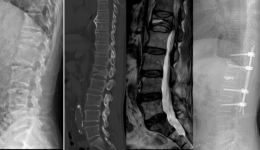

• 小切口完成大手术:脊柱转移瘤分离手术

小切口完成大手术:脊柱转移瘤分离手术

脊柱是恶性肿瘤最常见的骨转移部位,据统计在恶性肿瘤患者中,有30%-40%的患者出现脊柱转移。早期多无明显症状,随着病情的发展,约有10%的患者会出现转移性硬膜外脊髓压迫(MESCC),开始出现持续性的剧烈疼痛,逐渐进展到肢体麻木无力、瘫痪、大...